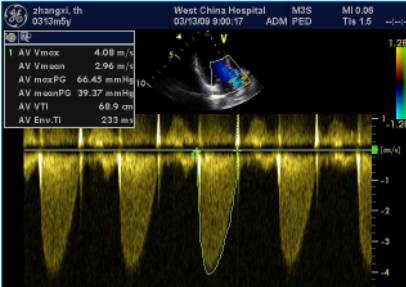

要获取主动脉瓣口前向血流速度和主动脉瓣口平均跨瓣压差,首先获取主动脉瓣前向血流的频谱。频谱通常是在心尖的长轴切面获取。获取时要注意让声束或者取样线与我们的主动脉瓣前向血流的方向一致,这样避免低估前向血流的速度和平均跨瓣压差。由于主动脉狭窄时,通过主动脉血流高速,所以我们常采用连续多普勒的方法来获取主动脉瓣前向血流的频谱。